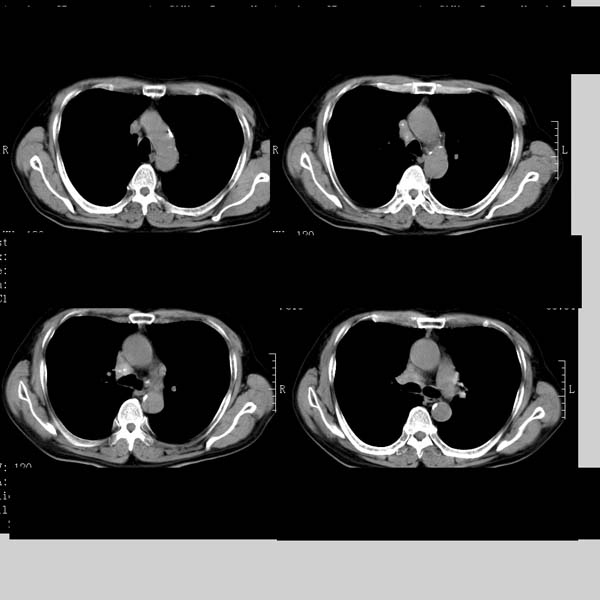

以下是引用守望可可西里在2008-6-24 1:11:00的发言:[br][br] 考虑为周围型肺癌:[br] 1.分叶结节,形态极不规则,蟹足样伸展的恶性浸润特征比较明确。[br] 2.磨玻璃影中由多个更高密度小结节聚集呈梅花瓣样。[br] 3.局部胸膜凹陷征比较明确。[br][br] 另:纵隔胸膜明显增厚、粘连。

以下是引用zjzjr在2008-6-24 11:19:00的发言:[br]支持左下肺周围型肺癌伴右肺转移,纵隔淋巴结转移,心包积液.

以下是引用zhangling在2008-6-24 14:56:00的发言:[br]我们科室意见报告为[br][br]1考虑左下肺周围型肺癌[br]2右肺小结节考虑转移瘤,纵隔淋巴结转移[br]3心包积液. [br] 各位老师分析的相当好 谢意[br]